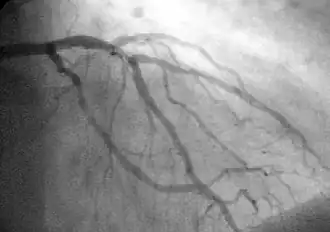

![]() A coronary angiogram showing the circulation in the left coronary artery and its branches. | |